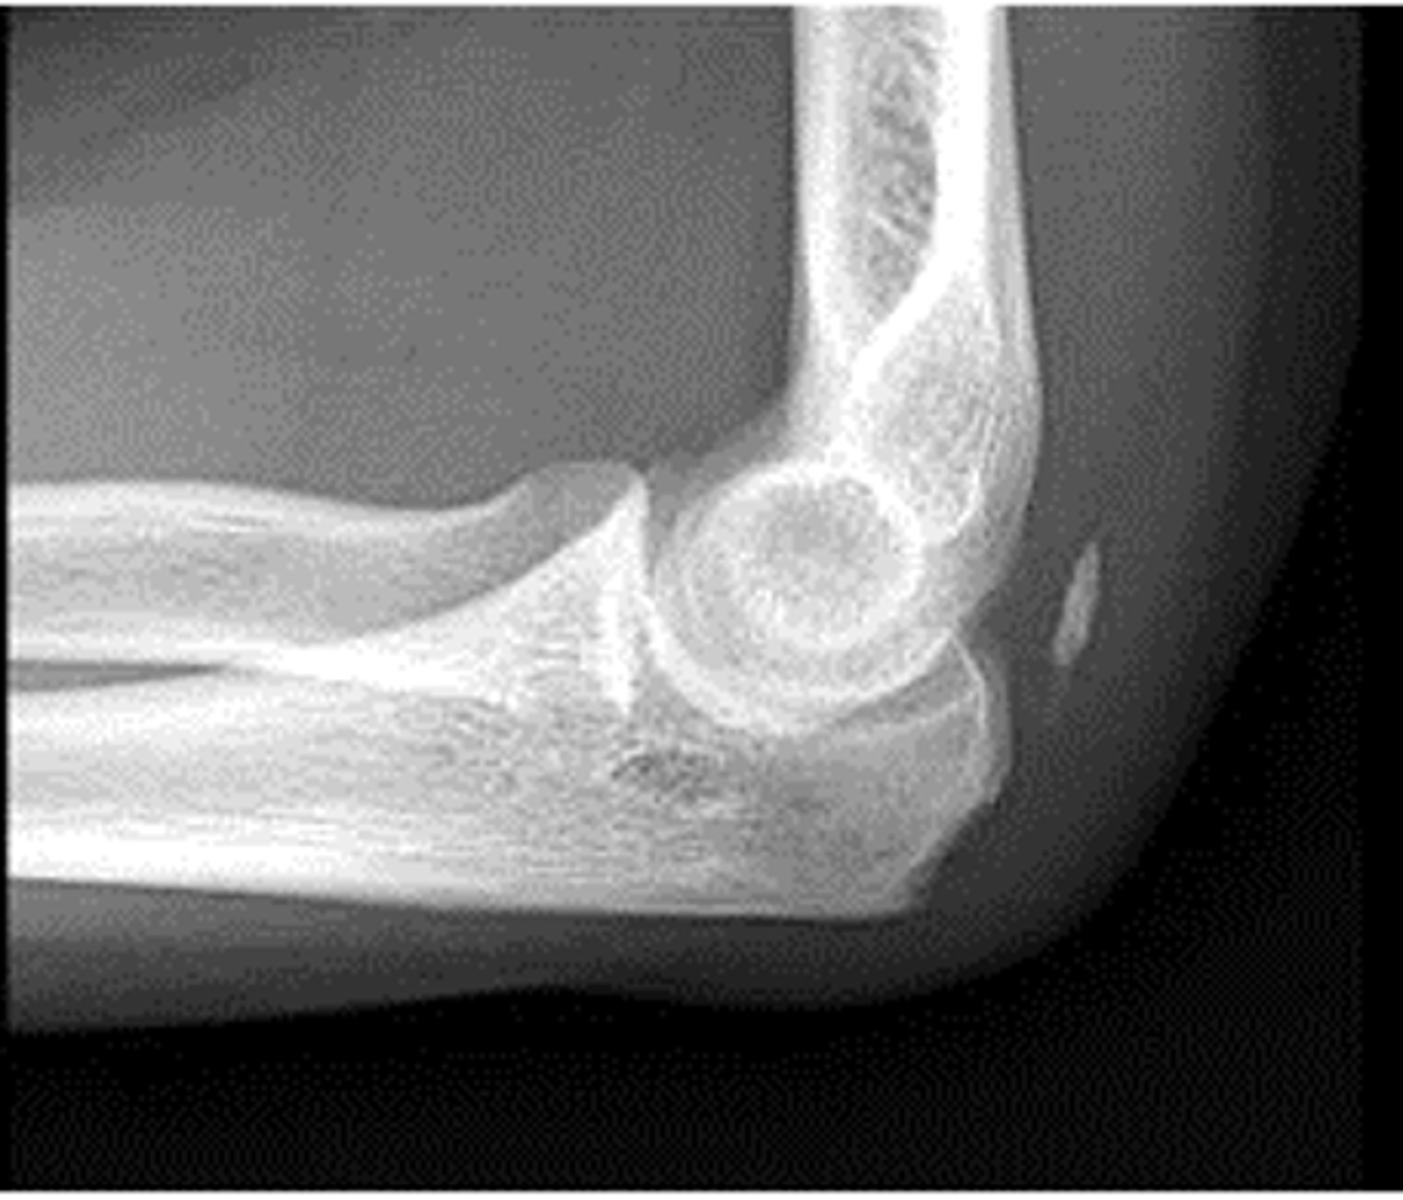

Lateral Elbow

Axial lateromedial for coronoid process elbow

Axial lateromedial for radial head elbow

fracture

scaphoid fat pad

pronator fat stripe